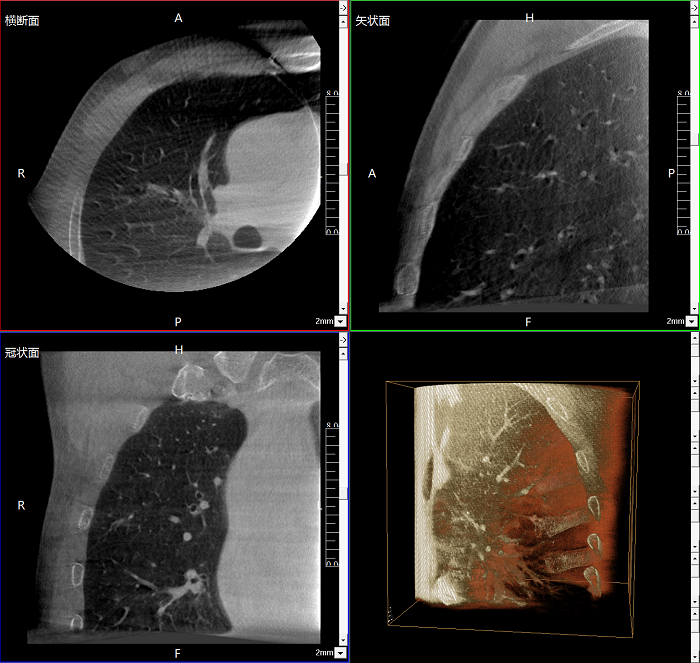

該設(shè)備可進(jìn)行快速的術(shù)中三維掃描,生成類(lèi)CT斷層圖像和立體3D圖像,保障植入物置入效果。廣泛適用于骨科、脊柱外科、矯形外科、創(chuàng)傷骨科等其他領(lǐng)域。

●極速成像僅需8秒,從數(shù)據(jù)采集結(jié)束到完成三維重建斷層影像